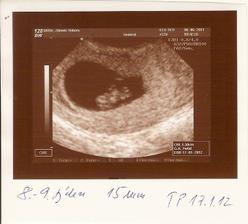

6.6.11 ko + odbery, 1,5cm, vsechno v poradku🙂